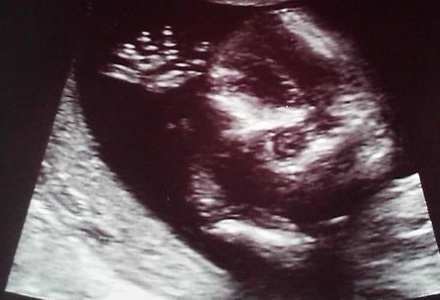

Atunci cand o mama isi vede copilul la o ecografie de sarcina, ii creste inima si un zambet imperturbabil ii invadeaza chipul. Unele ecografii nu sunt foarte clare, insa exista si cazuri in care bebelusii se vad foarte limpede si, spre amuzamentul viitoarelor mamici si al medicilor, sunt surprinsi in ipostaze care mai de care mai haioase.

Inveseleste-te cu cele mai amuzante ecografii de sarcina, pentru ca unele dintre ele te vor face sa razi in hohote!

Ecografii de sarcina amuzante